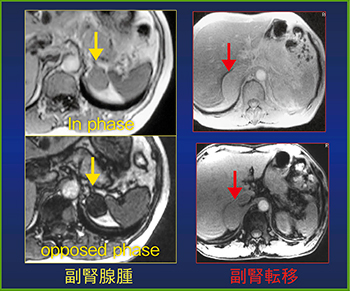

また,化学シフトMRIのopposed phaseで信号が下がれば副腎腺腫,下がらなければ転移と診断できる(図5)。CT値が30HU以上の場合は,造影CTを施行する。

図5 化学シフトMRIでの副腎腺腫と副腎転移の鑑別